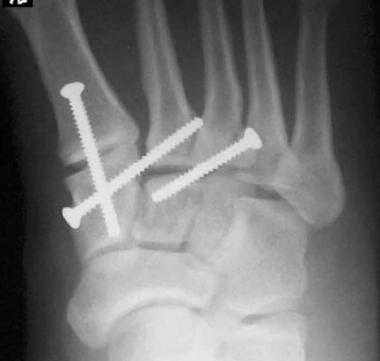

При смещении более 2 мм, нестабильности при функциональных тестах – рекомендовано открытое устранение вывиха с жёсткой фиксацией винтами или пластинами. Используются один или два продольных доступа в 1 и 2 межплюсневых промежутках. После обнажения первого предплюсне-плюсневого сустава первым этапом устраняется межклиновидная нестабильность, вторым этапом устраняется предплюсне-плюсневая нестабильность. В послеоперационном периоде сразу начинается разработка активного объёма движений. Нагрузку на стопу начинают постепенно, с тем чтобы полностью её восстановить к 6-8 неделе. Удаление спиц Киршнера производится через 6-8 недель, компрессирующих винтов через 3-6 месяцев. Возвращение к полной физической активности не ранее 9-12 месяцев после операции.

Открытое вправление вывиха, трансартикулярная фиксация 1-2-3 предплюсне-плюсневых суставов винтами.

(Справа) При КТ в сагиттальной плоскости визуализируется вывих 5-й плюсневой кости в сторону подошвы. Необычная травма была получена при езде на велосипеде. (Слева) При рентгенографии среднего отдела стопы в передне-задней проекции определяется односторонний вывих сустава Лисфранка: 1-5 плюсневые кости смещены латерально, переломы не выявляются.

(Справа) Этому же пациенту были выполнены открытая репозиция и внутренний остеосинтез. При рентгенографии среднего отдела стопы в передне-задней проекции видно, что для обеспечения стабильности суставов требуется фиксация множества костей. Следует отметить наличие винта, который выполняет функцию поврежденной связки Лисфранка.1. Общая характеристика: